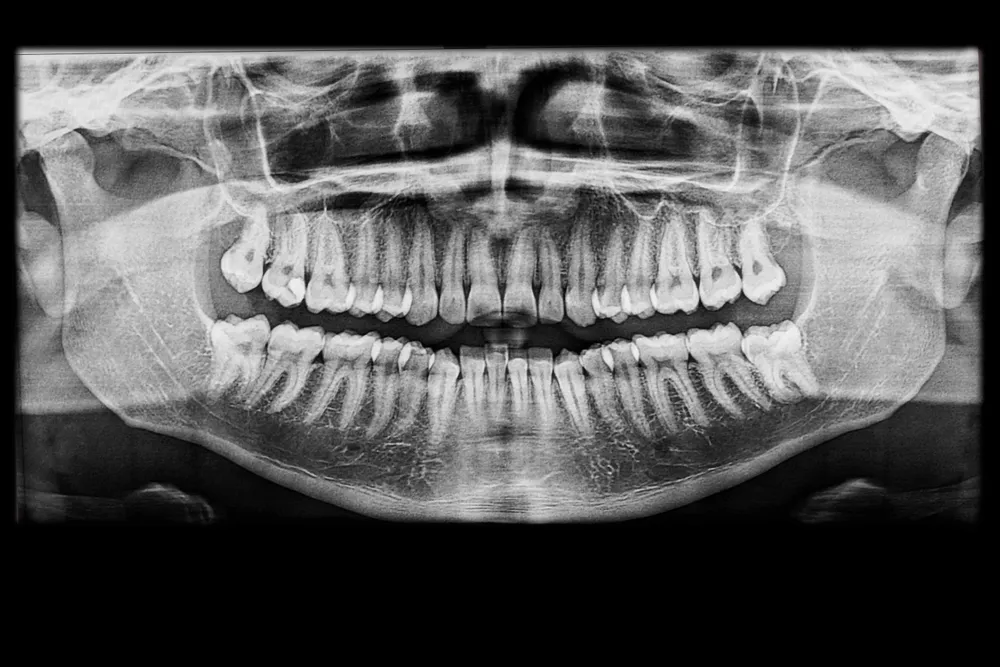

インプラント治療では、顎の骨の厚みや高さを立体的に把握することが重要です。そのため、歯科用CTを使って骨の状態を詳しく確認することがあります。

CTでは、骨の形だけでなく、神経や上顎洞の位置も把握しやすくなります。これにより、どの位置にどの角度で埋入するのが適切かを判断しやすくなります。レントゲンだけでは分かりにくい情報まで確認できるため、安全性を重視するうえでも大切な検査です。